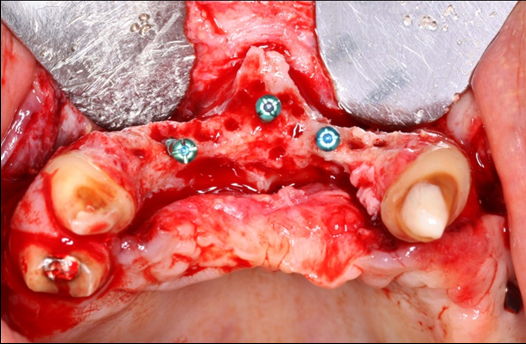

The surgical procedure was done under intravenous sedation using Fentanyl and Versed. Local anesthetic was used and a supra-crestal horizontal incision made on the palatal aspect of the anterior maxilla. A mucoperiosteal flaps were elevated, exposing a severely resorbed ridge of the pre-maxilla (Figure 2). Decortication was conducted with a round carbide bur in order to perforated the cortical aspect of the bone and expose the cancellous bone, to increase vascularity to the recipient site. Three screws were fixed parallel to the adjacent teeth, serving as “tent pole”. The screws had 14 mm length and approximately 6-8 mm of the tenting screws were exposed to the oral cavity (Figure 3). An absorbable collagen sponge (ACS) carrier/matrix was embedded with 12 mg of rhBMP-2 at 1.5 mg/mL (Infuse® Medtronic Sofamor Danek, Memphis, TN, USA) and allowed to absorb for approximately 20 min. The rhBMP-2/ACS was cut into strips, half of the strips were added to the natural bone mineral component derived from bovine bone (Geistlich Bio-Oss® granules small - 0.25 to 1 mm, Geistlich Pharma, Germany). Initially, some strips of rhBMP-2/ACS were placed over the buccal aspect of the residual alveolar ridge of the pre-maxilla, followed by strips mixed with bovine bone (Figure 4). The three screws were fully covered by rhBMP-2/ACS strips. Finally, a titanium mesh was adapted over the entire rhBMP-2/ACS graft and fixed with 2 monocortical screws, one on the buccal aspect and one on the palatal aspect of the ridge, respecting a 2 mm distance from the mesh to the adjacent teeth (Figure 5). Extensive undermining incision was conducted on the apical aspect of the buccal flap in order to achieve primary closure.

Figure 2.Occlusal view of the pre-maxilla after elevation of amucoperiosteal flap. Noteright and left pre-maxilla buccal plate concavities due to severely resorbed ridge. The central tenting screw is located mid-way into the nasal spine.